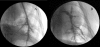

Figure 3.

(A) Pulmonary arteriogram in a normal, nonhypertensive micropigs. (B) Left pulmonary artery angiograms after development of systemic level pulmonary arterial hypertension, showing proximal dilation, peripheral tortuosity, and marked pruning with loss of branching vessels.